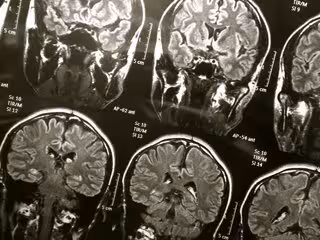

Cerebro

Cerebro - FLICKR/WYINOUE - Archivo